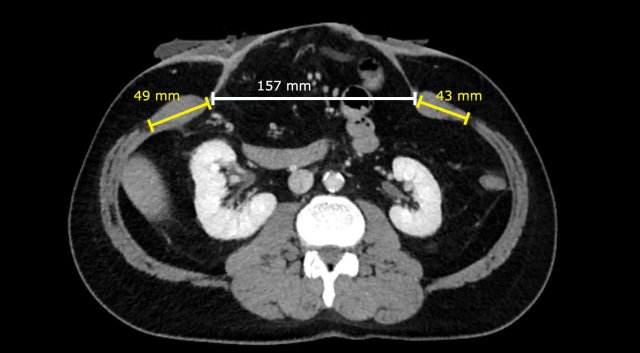

Image

In this patient the Rectus to Defect Ratio: (49 mm + 43 mm) / 157 mm = 0.58.

This ratio predicts that hernia closure will probably not be possible without performing a component separation technique.